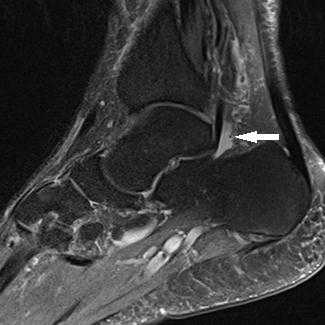

Прежде всего, это боль по задне-внутренней поверхности голеностопного сустава. Возможно «защёлкивание» большого пальца при его сгибании. Хруст, крепитация по задне-внутренней поверхности голеностопного сустава при активных движениях. При физикальном осмотре определяется боль при сгибании большого пальца через сопротивление, при форсированном подошвенном сгибании в голеностопном суставе, при этом боль отсутствует в области первого плюсне-фалангового сустава. Для диагностики повреждения сухожилия длинного сгибателя большого пальца стопы целесообразно выполнение МРТ, при этом обнаруживается скопление жидкости вокруг сухожилия на уровне голеностопного сустава, изменение сигнала от самого сухожилия.

МРТ наиболее полезный метод исследования сухожилий вокруг голеностопного сустава и выявления повреждений. Другие диагностические тесты включают сканирование костей и введение радиоконтрастного вещества в сухожильное влагалище.